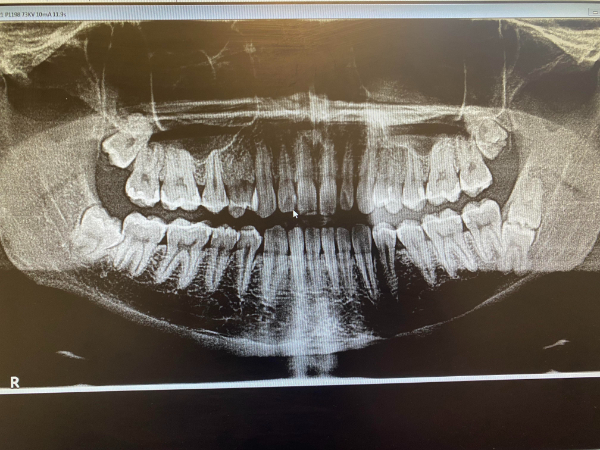

Meanwhile panoramic X-rays capture your entire mouth and jaw in one image.

On average a panoramic dental X-ray will cost you about 130. If a child has no history of cavities or active tooth decay they should probably get x-rays once every 12-36 months or so depending on any signs of problems. This image is a panoramic x-ray of a child.

You may have a dentigerous cyst on tooth 1 which is your top right wisdom tooth or the tooth on the top left of the xray. Retained baby teeth and missing premolars is very common. Baby teeth xray reddit a child s face before the baby teeth fall off.